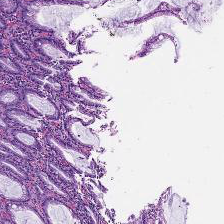

For Target Domain, the MHIST dataset [2] is used (available at https://bmirds.github.io/MHIST/ ), which contains high quality H&E stained histopathology images suitable for learning realistic color and texture distributions.Jana The dataset contains 3,152 H&E images. Some examples are displayed in Figure 1.

The Figure 3 shows virtual H&E generation from light-sheet microscopy image. Each column represents a different type of image. Each row corresponds to a different slice. From these images, it can be observed that the CycleGAN has learned to map the nuclear and cytoplasmic signals to the characteristic H&E colors. Overall tissue morphology and structure are largely preserved, demonstrating that the model captures the spatial relationships of nuclei and cytoplasm from the fluorescence channels.

The Figure 4 illustrates how CycleGAN outputs evolve across training epochs. Each column shows the virtual H&E image generated at a specific epoch, while each row corresponds to the same slices. Early in training, the images may exhibit incomplete or uneven staining and less clear tissue structure.

As training progresses, the representation of H&E changes slightly and becomes visually more consistent. However, through comparison across epochs, it can also be observed that the CycleGAN generated results exhibit certain drawbacks, including variability in staining intensity, occasional loss of fine structural details, and the introduction of artificial texture patterns that are not present in the original fluorescence images. Due to the lack of ground truth H&E images, the quality of the generated virtual H&E cannot be quantitatively validated in this study and is assessed primarily through visual inspection. If paired ground truth H&E data were available, quantitative performance metrics such as cell count agreement or dice score and intersection of union (IOU) of the stained cells (positive cells) in the virtually generated image with respect to the real image [2].